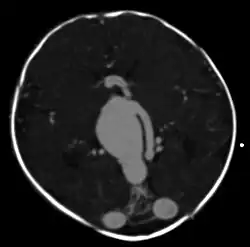

vein of Galen malformation